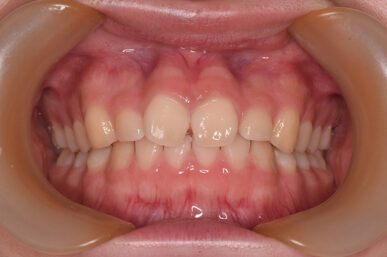

前歯のガタツキと隙間が気になる

After

ライト1で治療しました。

前歯のみの問題で奥歯に問題がありませんでしたので、費用も期間も少なく治療できました。

治療期間

6ヶ月

治療費用

550,000円(税込)